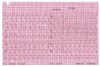

Premature ventricular contraction (unifocal)

Hyperkalemia

Ventricular Fibrillation

Atrial Flutter

Trosades de pointes

Right bundle Branch Block

Premature Ventricular Contraction (PVC)

1st degree AV block

Multifocal PVC

Polymorphic Ventricular Tachycardia

Ventricular Flutter

Ventricular tachycardia

Multifocal Atrial Tachycardia

Monomorphic Ventricular tachycardia

Atrial Fibrillation